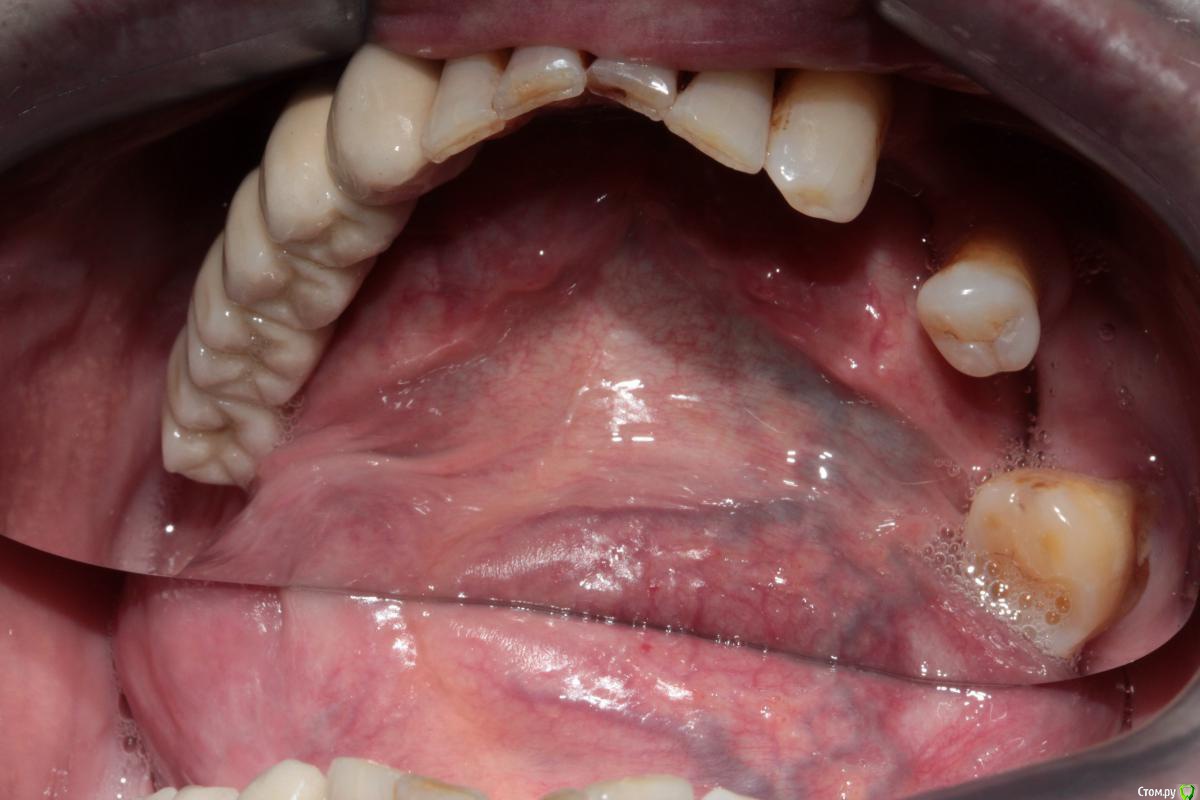

Здравствуйте уважаемые коллеги. Прошу у Вас совета какой план лечения вы бы рекомендовали данному пациенту.

Сразу замечу, я сначала рассматривал вариант с ортодонтией (чтобы собрать все зубы вместе) а далее в отсутствующие места имплантация. Но, пациент не в силах оплатить это лечение. Так как пациент мой бывший учитель, я хочу ему помочь, сделать работу которая материально минимально затратна и функционально его обеспечит.

37ой зуб я уже удалил, сначала сделал ревизию, обнаружен был кариес корня по фуркации, поэтому удалили. На данный момент пациент не может полноценно жевать.

Меня больше смущает 2 момента, 1й - это то что на верхней челюсти зубы "разбросаны" как попало, не знаю что можно сделать не собрав их вместе предварительно. 2ой - в 4ом сегменте мост, консольный, его снимать не хочется, так как его по сути недавно поставили, а не сняв его не знаю что можно сделать в 3ем сегменте, если имплантацию откидываем как вариант....

Был предложен вариант сделать бюгель, с обычными кламмерами на верхней челюсти, как думаете при таком расположении зубов, это правильно?